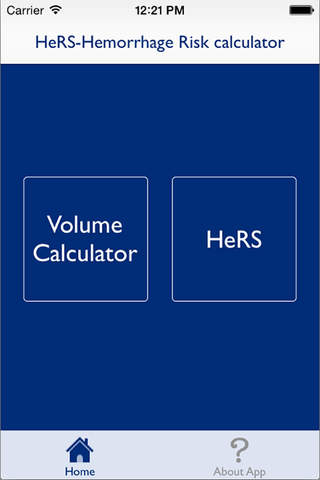

The HeRS (Hemorrhage Risk Stratification) calculator is an application that aids in determining the probability of hemorrhagic transformation of acute ischemic stroke in patients with an indication for anticoagulation. It is a prospectively validated score.

The HeRS score is a prospectively validated equation based on continuous variables of age, renal function, and stroke size. The equation is complex and cannot be performed easily or quickly with paper or with an ordinary calculator. Determining the probability of hemorrhagic transformation of acute ischemic stroke is clinically useful as risk of hemorrhage often needs to be weighed against risk of recurrent stroke in deciding on whether or not to anticoagulate in the acute clinical setting. The HeRS score provides one of these valuable pieces of data- the likelihood of hemorrhagic transformation. Using the mobile application, the HeRS score can be accurately and easily determined rapidly.

The HeRS score is a prospectively validated equation based on continuous variables of age, renal function, and stroke size. The equation is complex and cannot be performed easily or quickly with paper or with an ordinary calculator. Determining the probability of hemorrhagic transformation of acute ischemic stroke is clinically useful as risk of hemorrhage often needs to be weighed against risk of recurrent stroke in deciding on whether or not to anticoagulate in the acute clinical setting. The HeRS score provides one of these valuable pieces of data- the likelihood of hemorrhagic transformation. Using the mobile application, the HeRS score can be accurately and easily determined rapidly.